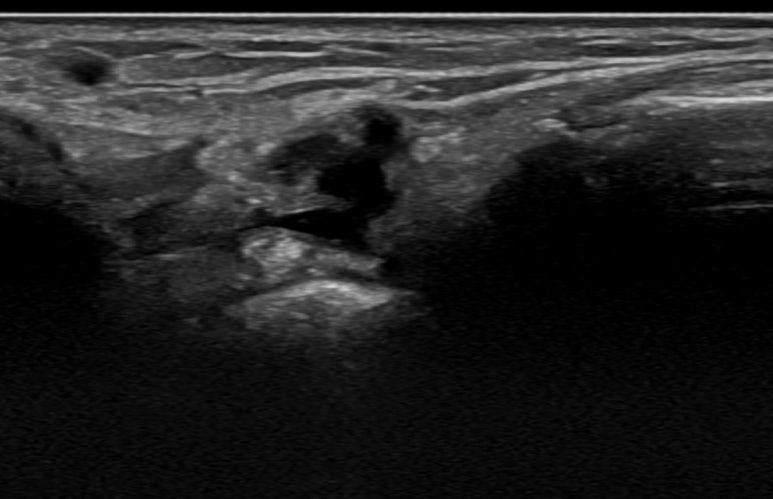

좌측 손목 / 우측 손목 ## 증상이 없는 좌측 손목의 영상은 표준 초음파 영상과 동일한데요.

통증이 있는 우측 손목**의 영상으로 표준초음파 영상과 달리 까만 덩어리가 보입니다.

초음파상 결절종을 확진할 수는 없지만 양방 초음파 검사상에서 이미 결절종으로 추정진단을 받고 내원하셨고, 한의학적으로 습비증으로 진단하였는데요.